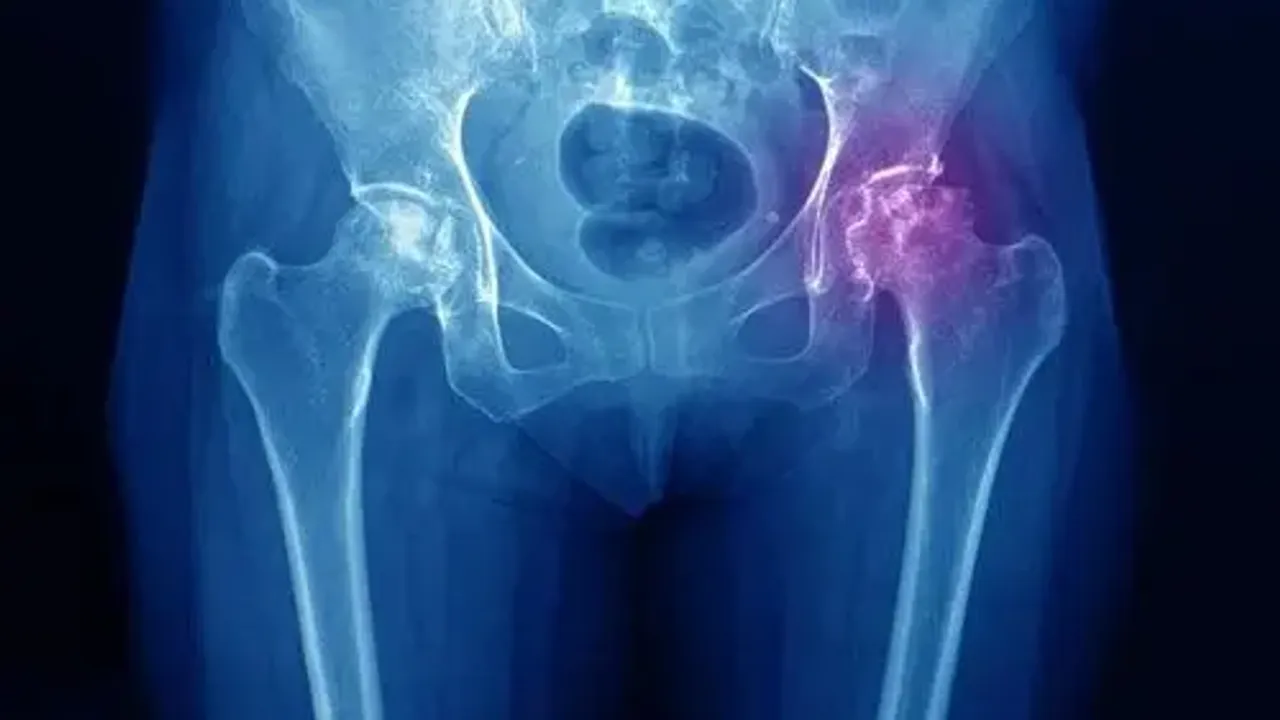

AVN’nin özellikle travma ya da kortizon gibi ilaçların uzun süreli kullanımıyla tetiklendiğini belirten Dr. Karaaslan, kalça ekleminin vücudun en büyük yük taşıyıcı eklemlerinden biri olduğunu hatırlattı. Bu eklemde kan akışının kesilmesi, özellikle femur başı olarak bilinen uyluk kemiğinin tepe kısmında ciddi problemlere yol açmakta. Kan akışının durması bu bölgedeki kemik dokusunun beslenememesine ve yavaş yavaş ölmesine sebep oluyor. Başlangıçta hafif rahatsızlıklarla kendini belli eden bu hastalık, zamanla ağrının şiddetlenmesine ve hareket kabiliyetinin kısıtlanmasına yol açıyor.

Cerrahi yöntemler arasında en etkili olanlarından biri olan core dekompresyonun, femur başına küçük delikler açılarak basıncı azalttığını ve kan akışını teşvik ettiğini ifade eden Dr. Karaaslan, osteotomi ile kemikte yapılan kesilerin, eklemin pozisyonunu değiştirerek sağlıklı kemik dokusu üzerine daha fazla yük bindirdiğini belirtti. Hastalığın ileri evrelerinde kalça protezi uygulamasının kaçınılmaz hale geldiğini söyleyen Karaaslan, bu durumda hasarlı eklemin çıkarılarak yerine yapay bir eklemin yerleştirildiğini kaydetti.